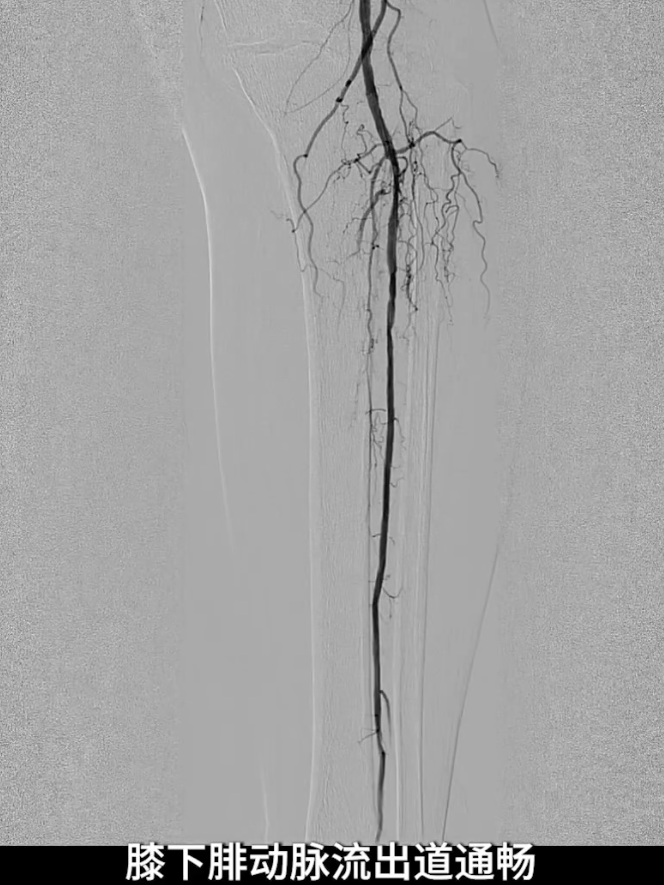

流出道扩张与优化:使用3.0×200mm PTA球囊对“胫腓干-腓动脉”全程进行扩张;

更换0.014系统导丝,经交通支选入胫后动脉远端,

再以2.0×40mm球囊扩张残余狭窄,并压迫远端逆行穿刺点止血,确保膝下流出道通畅。

术后造影验证:股浅动脉管腔恢复通畅,无明显残余狭窄,局限夹层未对血流造成影响,无需植入补救性支架;膝下腓动脉流出道通畅,胫后动脉至足底动脉血流连续,足部血流灌注显著改善。